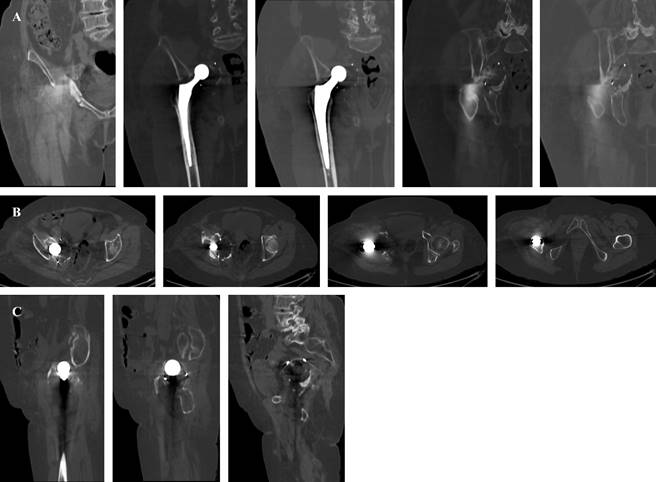

Femenino de 82 años. Sin antecedentes clínicos de importancia, salvo por una artroplastía total de cadera derecha cementada hace un mes. Acude por dolor en cadera derecha e incapacidad a la deambulación. La paciente refiere dolor en cadera derecha que limita realizar fisioterapia y no tolera bipedestación ni sedestación. Examen físico: paciente no deambula. Miembro inferior derecho: cadera: presencia de herida cicatrizada de aproximadamente 12 cm. Rangos de movilidad no valorables por dolor, limitados. Acortamiento clínico de 1 cm neurovascular distal conservado. Harris Hip Score (HHS) de 16 puntos y escala visual análoga (EVA) de 8/10. Se solicitaron estudios radiográficos complementarios (Figura 1).

Figura 1: Radiografía anteroposterior de pelvis, obturatriz y alar de cadera derecha, se evidencia migración medial intrapélvica de componente acetabular.

Con los hallazgos encontrados se solicitan estudios de imagen adicionales (Figuras 2 y 3).

Figura 2: Tomografía de pelvis, se observa migración medial intrapélvica de componente acetabular y fractura acetabular transversa: A) corte coronal, B) axial y C) sagital.

Figura 3: Reconstrucción 3D de tomografía contrastada, se evidencia ausencia de lesión de grandes vasos por migración medial intrapélvica de componente acetabular.